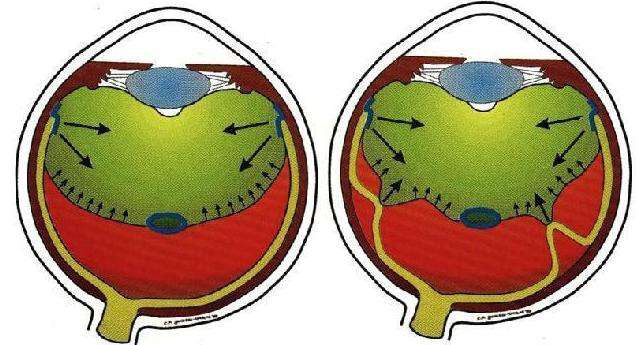

A:飛蚊症是指眼前有飄動的黑影,尤其是看白色背景的時候症狀更加明顯,同時有時候有些人會伴有閃光感,眼前一亮一亮的症狀,引起的原因主要是玻璃體液化和後脫離。絕大多數的飛蚊症都是生理性,但是有大約20%的飛蚊症,可能是病理性,具有威脅視力下降的情……

A:飛蠅症又稱飛蚊症和玻璃體混濁,是指玻璃體內出現不透明體,造成患者視物出現模糊。人出生時玻璃體呈凝膠狀態,是重要的屈光介質,正常的玻璃體隨著年齡逐漸出現液化,從而導致玻璃體混濁。此外,一切玻璃體混濁是由於病理原因所導致,例如玻璃體出血、葡萄……

A:眼前出現飛蚊的症狀往往是因為玻璃體發生了液化、變性和混濁,通常情況下玻璃體的混濁,比較多見於近視眼的人和年歲比較大的中老年人,還要特別重視的一個問題是當眼底有病變發生的時候,也會出現玻璃體的混濁、玻璃體混濁的加重,這時候眼前飛蚊的症狀需要做……

A:眼睛裡有飛蚊的現象主要是因為玻璃體發生了液化、變性和混濁,玻璃體原本在眼睛裡邊是一個膠凍狀的結構,由於近視眼以及中高度近視或者年齡過大了,中老年人就會出現玻璃體的液化、變性和混濁,這種情況下很難通過任何治療,將已經液化的玻璃體恢復到膠凍狀的……